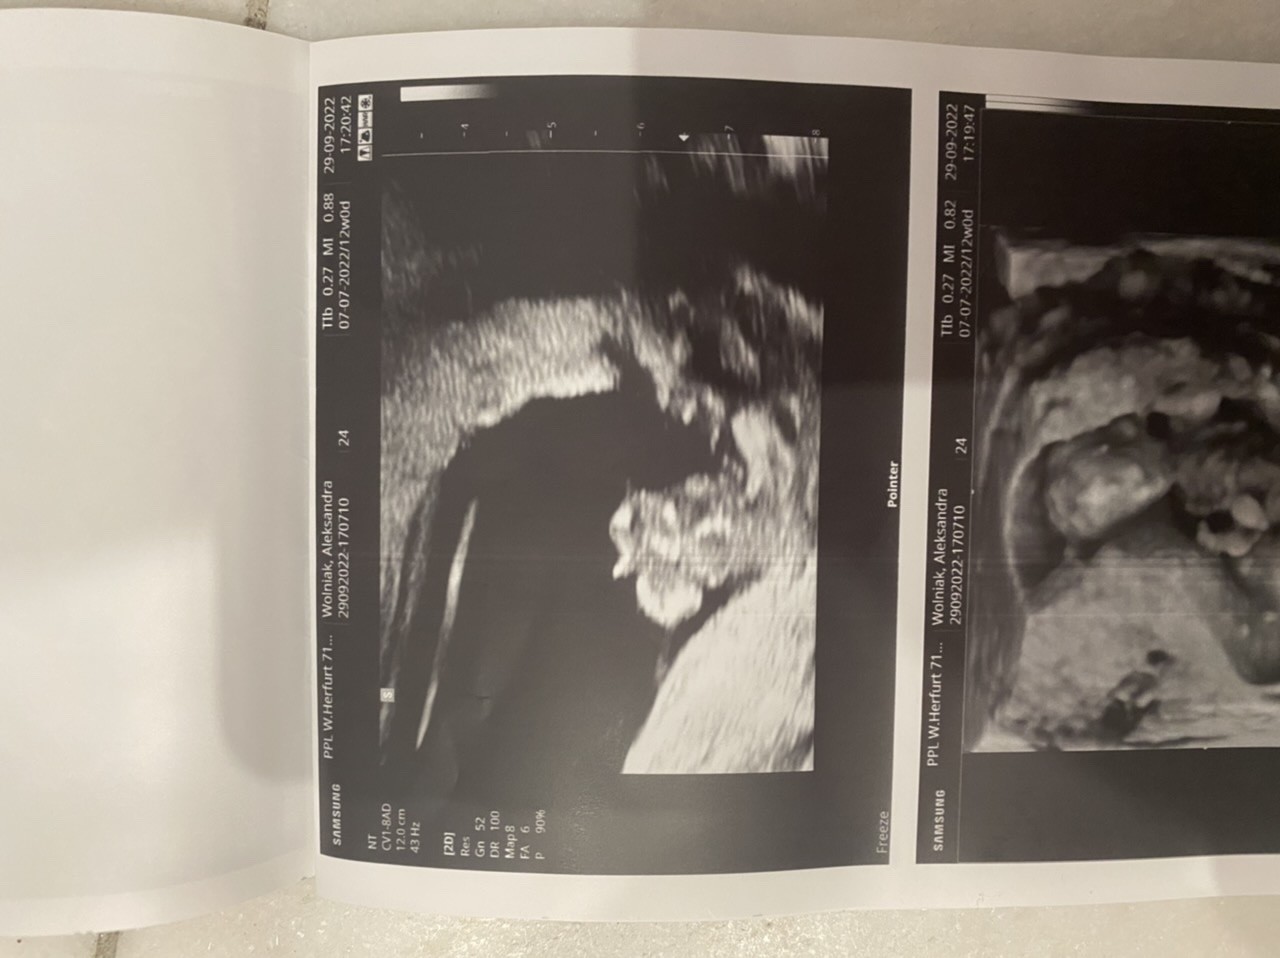

Chłopak czy dziewczynka?

W 13 tygodniu lekarz mówił że raczej chlopczyk